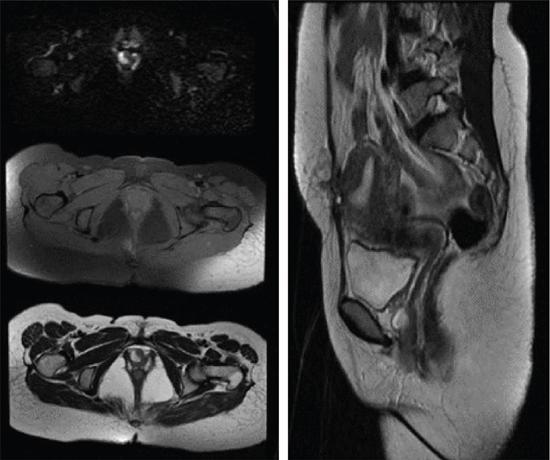

VAGINAL CYSTS Sumeena The vagina is a fibromuscular sheath. Vagina extends from uterus to the vulvar vestibule. The vagina is located in the middle compartment of the pelvis and it is related anteriorly to bladder and urethra, posteriorly to lower rectum and anal canal. The length of vagina ranges from 4 to 12 cm. The posterior wall of vagina is longer and it ends in posterior fornix; the anterior wall is shorter and ends in the anterior fornix. The wall of vagina is composed of three layers: (a) The mucosa consists of nonkeratinized stratified squamous epithelium without glands and its hormone sensitive layer; (b) the muscularis made up of connective tissues and smooth muscle; and (c) the adventitia, which is fascia that connects the vagina to the surrounding pelvic structures and maintains support. The prevalence of vaginal cysts is estimated to be less than 1%. They typically present in the age of 30–40s. Their origin may be Müllerian, Wolffian, squamous or urogenital. Risk factors for vaginal cysts: The vagina may be underevaluated due to probe positioning in routine pelvic US and due to poor vaginal tissue characterization in CT examinations. Though MR imaging provides good tissue characterization, we must focus on the vaginal region to identify any incidental findings. The strengths and limitations of each imaging modality must be understood in assessing the vagina. US is the first-line imaging modality since it is readily available, cost-effective, high resolution and no ionizing radiation. Limitations include operator dependence and patient obesity. The major limitation with transabdominal approach is that the upper portion of the vagina is seen well; the inferior aspect of the vagina is obscured due to shadowing from the pubic symphysis. Limitation with transvaginal US is that the transducer is typically placed in the anterior or posterior fornix which bypasses the perineum and vagina. US imaging needs methodic evaluation performed from introitus to the fornices and include transabdominal, transvaginal and translabial approaches. Due to the poor vaginal tissue characterization and ionizing radiation, CT is usually not indicated for evaluation of the female pelvis. When US is inconclusive, pelvic MR imaging is recommended. The vaginal wall anatomy is best imaged with T2-weighted sequences. The vaginal mucosa has high signal intensity, circular and longitudinal muscle layers have intermediate signal intensity. Embryonic Traumatic Epithelial inclusion cyst/epidermal inclusion cyst/squamous inclusion cyst Skene’s duct cysts Urethral diverticulum Infective Filariasis Vaginitis emphysematosa Epidermoid cyst Sebeceous cyst Endometriotic cyst Ciliated cyst Paraurethral mass Rare Lymphangioma Postradiation Haematocolpos Rectocele and cystocele Prolapsed ectopic ureterocele Large nabothian cyst, tunnel cluster cysts Adenoma malignum Most common type of vaginal cysts, almost up to 40% of cystic masses. As Müllerian epithelial tissue can present anywhere in the vaginal wall, the cysts can also be found anywhere within the vaginal walls. Most common location is along the anterolateral aspect of the vagina. Müllerian cysts present as small, midline cystic masses, with no symptoms and require no treatment. Symptomatic vaginal cysts are treated by excision. The entire cyst wall must be removed to prevent recurrence. Adenocarcinoma can arise in a Müllerian vaginal cyst. The epithelium of Gartner’s cysts is devoid of cytoplasmic mucicarmine and PAS-positive material, in contrast to the epithelium of Müllerian cysts. MRI – Gold standard. Mucus secretion is a unique feature of Müllerian cysts and shows heterogeneous T2 signal. Extent of the cyst, surrounding structures are better evaluated in MRI prior to surgery. Incomplete regression of Wolffian ducts leads to the development of Gartner duct cysts. They are usually noted in the upper anterolateral wall of the vagina above the inferior border of the pubic symphysis. Typically less than 2 cm. When these cysts are large enough, they can compress the urethra causing urinary symptoms. It can also be associated with abnormalities of the metanephric urinary system such as an ectopic ureter, unilateral renal agenesis and renal hypoplasia. USG: Anechoic structure in the upper vagina; transvaginal US provides better differentiation than the transabdominal approach. Fig. 11.19.1.1; T2-axial image shows hyperintense cystic lesions, one in posterior fornix and another one in anterior aspect of upper vagina. Both the lesions are above the level of pubic symphysis. Fig. 11.19.1.2; T2-sagittal image shows hyperintense cystic lesions, one in posterior fornix and another one in anterior aspect of upper vagina. Both the lesions are above the level of pubic symphysis. Bartholin glands are commonly located posterolateral to the vaginal introitus and medial to the labia minora. The obstruction of the gland’s duct either by a stone or a stenosis, which may be caused by prior infection or trauma, leads to Bartholin gland cysts. Cysts are typically round and unilocular, seen at or below the level of the pubic symphysis, usually asymptomatic. This is most apparent on coronal plane imaging. USG: Bartholin gland cysts can be imaged by a transperineal approach. Although these cysts are usually asymptomatic, occasional infection may necessitate drainage of the cysts (Fig. 11.19.1.3). Bartholin gland duct can be obstructed due to stone or stenosis, later which can become infected. The Bartholin’s gland abscess size ranges from 2 to 8 cm with an average of 3 to 4 cm. Antibiotics with or without surgical drainage is the treatment. Marsupialization may be needed in recurrent conditions. USG-complex cystic hypoechoic to anechoic lesions increased throughout transmission. Colour Doppler may show peripheral hyperaemia. Spectral flow – low resistance arterial flow. MRI-T2: Tends to show heterogeneous signal T1 C+ (Gd): pericystic enhancement may be seen (Fig. 11.19.1.4). Vaginal inclusion cysts – also known as epidermal inclusion cysts, most commonly are seen in the distal posterior or lateral vaginal wall at sites of previous trauma or surgery. Inclusion cysts are lined by a stratified squamous epithelium and contain keratinous material. Symptomatic cyst needs treatment. The treatment of choice for symptomatic cysts is marsupialization. MRI-DWI shows restriction (Fig. 11.19.1.5). Skene glands are paired structures in periurethral location near external urethral meatus with ducts draining into the urethra. Skene gland cysts can cause UTI or urethral obstruction. They are distinguished from urethral diverticulum, which are usually midurethral. In T2-weighted images, Skene duct cysts seen as round or oval hyperintense lesions just lateral to the external urethral meatus. MRI:T1 hyperintense due to proteinaceous material. T2 hyperintense. Fluid–fluid level if complicated with debris or haemorrhage (Fig. 11.19.1.6). It may be congenital or result from infection or obstruction. In females, diverticula commonly extends from the posterolateral wall of the mid-portion of the urethra. During voiding cystourethrography (VCUG), they are seen best on postvoid images. Transrectal US shows a cystic mass in proximity to the urethra and it will be seen anterior to the vagina. Lack of radiation and capacity to differentiate solid from cystic masses is the advantage of US over CT. CT shows a periurethral lesion with low attenuation. MRI shows T1 hypointense and T2 hyperintense fluid signal intensity. Postcontrast imaging with gadolinium is used to evaluate infection or inflammation. Adenoma malignum of the cervix is a rare variant of cervical mucinous adenocarcinoma. VAGINAL MALIGNANCIES Rupa Renganathan, Suchana Kushvaha The primary vaginal carcinoma is a very rare gynaecological malignancy and accounts for 2%–3% of genital tract malignancies and 10% of all vaginal malignancies. It is defined as a cancer found in the vagina without histological or clinical evidence of cervical or vulvar malignancy and without previous history of treatment of cancers in the last five years. The commonest primary carcinoma is squamous carcinoma, and other rare primaries are adenocarcinoma, melanoma and sarcomas. The secondaries in the vagina are much more common than the primary and account for more than 80% of vaginal malignancies. Primary vaginal carcinoma is common in elderly, however, seen in the younger women when associated with human papillomavirus (HPV 16 and 18). Vaginal carcinomas are staged based on FIGO classification. Management of the cancer is usually based on the stage of the disease and the histological subtypes. Vagina is an elongated fibromuscular structure connecting the uterus with the vulva. It is approximately 7–9 cm long. The long axis is oriented 90 degrees to the uterine axis and its upper part is oriented almost horizontally and in plane with the pelvic floor. It is lined by the nonkeratinizing stratified squamous epithelium. It has anterior, posterior and lateral walls. The upper portion of vagina is invaginated by the cervix such that a space is created between its walls and the cervix called fornices. The posterior fornix is deeper than the anterior fornix. Anterior wall is separated from the bladder base and the urethra by the anterior vesicovaginal septum while the posterior wall is separated from the rectum by rectovaginal septum. The posterior fornix is covered with the peritoneal reflection that forms the Pouch of Douglas. It is supplied by the vaginal arteries, originating from the internal iliac artery and branches of uterine, middle rectal and inferior vesical arteries. There is considerable overlap in the lymphatics between the various parts of vagina. The upper two-thirds of the vagina drain into the pelvic lymph nodes that include external, internal and common iliac groups and the lower third into the superficial inguinal and femoral lymph nodes. The posterior vaginal wall also drains into the perirectal lymph nodes. MRI is the standard imaging modality for local staging of cancers and also for assessment of treatment response and surveillance due to superior soft tissue resolution, multiplanar capability. In a relaxed state, it is seen as a ‘H’ shaped structure posterior to urethra with the anterior and posterior walls being opposed to each other. The vaginal lumen may have secretions or blood-causing distention of its lumen. The anatomy of the vagina is best depicted on T2w images where three layers of its wall can be distinguished in a nondistended state. The mucosa is T2 hyperintense with a hypointense submucosal and muscularis layer beneath it. It is surrounded by adventitia which is hyperintense due to the venous plexus (Fig. 11.19.2.1A and B). For accurate staging purposes, vagina should be distended with ultrasound gel with the help of a syringe and infant feeding tube (Fig. 11.19.2.1C and D). Before inserting gel, patient consent must be taken and her marital status should be enquired. Care must be taken that air is not insufflated while introducing the jelly. Jelly can also be introduced in patients other than carcinoma vagina in cases where vaginal involvement is suspected in other malignancies. After adequate distention, the walls get separated and the fornices are better delineated. For staging purposes, the vagina is divided into three parts. The upper one-third lies above the level of the bladder base and includes the fornices. The middle one-third is opposite to the bladder base and the lower one-third opposite to the urethra (Fig. 11.19.2.1D). Ultrasound owing to its limited field of view and inaccurate staging is not used for imaging of vaginal pathologies. CT has poor contrast resolution and is used only for lymph nodes staging in known patients of vaginal malignancy. PET CT has the advantage in that it combines both the functional and anatomical information about the tumour. While performing PET for the gynaecological malignancies, general measures to reduce bladder activity, like Foley’s catheterization, IV hydration and diuretic administration, are adapted and the image acquisition is done from the pelvis cranially. The advantage of PET beyond providing functional information is that it provides information about distant metastases. The presence of nodal metastases in patients with vaginal cancers portends a poor prognosis and alters the management. In a study by Christensen et al., PET CT was found to be more sensitive and carried greater negative predictive value as compared to MRI for detection of lymph nodes. However, commonly seen inflammatory and the reactive lymph nodes may show uptake. Node biopsy or excision is mandatory wherever the metastatic involvement is indeterminate or questionable. PET CT is recommended for restaging the recurrent tumour, and differentiating the treatment changes from recurrence in vaginal carcinomas. In cases of vaginal sarcomas, it is used for grading, staging and follow-up imaging. MRI is the main investigation for evaluation of vaginal masses and for both staging and surveillance. Patients are requested to be fasting for at least 4 hours to limit bowel motility and to empty the bladder 1 hour before the study to achieve moderate distention of the bladder. Use of antispasmodic agents like Butylscopolamine 40 mg IM/IV or Glucagon 0.5–1 mg IV/IM can also be considered to reduce bowel movements. The vagina should be distended with about 60 mL of Ultrasound Gel for evaluation of vaginal lesions. The patient is imaged in supine position with phased array abdomino pelvic coil. The saturation band is usually placed anterior and superior to the field of view. T2 imaging remains the mainstay for evaluation of vaginal tumours. The basic sequences for evaluation of vagina lesions are T2 sagittal, axial, coronal and oblique axial, T1 axial and diffusion-weighted imaging in axial plane. The high-resolution oblique axial along the plane of vagina is the best sequence which demonstrates the tumour and its extent. The study may be completed by contrast injection. The sequences for contrast evaluation will include pre-T1 with fat saturation, followed by dynamic contrast injection and postcontrast T1 fat saturated acquisition. The most common clinical presentation would be painless vaginal bleeding (65%–80%) followed by vaginal discharge, pelvic pain, urinary symptoms and mass being felt in the vagina. The primary carcinoma are usually squamous cell carcinoma and accounts for about 80% of cases. They are more commonly seen in the upper third in the posterior wall. It is associated with HPV and about 30% of women also have history or associated intraepithelial and invasive cancers of cervix and vulva. About a third of patients present with lymph nodal metastasis in the pelvis or inguinal region at the time of clinical presentation. Adenocarcinoma accounts for only 9% of primary vaginal malignancies, and they are usually seen in the anterior wall of the upper third of the vagina. They affect younger age group (14–21 years) and arise from the lesions such as endometrial deposits and the vaginal adenosis. About two-thirds of the cases have exposure to Diethylstilbestrol to their mothers. When seen in older women, they are usually clear cell carcinomas. Staging of vaginal carcinoma with MRI parallels clinical FIGO staging (Figs 11.19.2.2–11.19.2.4). The tumour is best seen on T2-weighted sequences where it is seen as an intermediate signal (higher than muscle and lower than fat). Adenocarcinomas typically exhibit high T2 signal. Because of the signal on T2, the tumour is well delineated from the vaginal wall which displays low signal intensity. When the tumour is limited to vagina, it is difficult to be seen on T1 sequences unless it causes a contour abnormality as the tumour will be isointense on T1. Stage I tumours are those which are either seen as mass/plaque like thickening but will be limited to vagina and will be diagnosed if the hypointense T2 signal of the vaginal wall is preserved (Fig. 11.19.2.5). When the tumour disrupts this hypointense layer and extends into the paravaginal fat, the staging becomes Stage II (Fig. 11.19.2.6). The loss of normal signal of the vaginal wall should be looked at all three orthogonal planes to identify subtle loss of the signal which is the important finding which upstages the tumour.